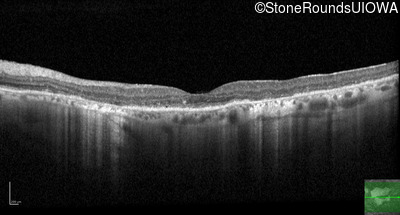

Optical Coherence Tomography - Left - 20/40 +2

Exemplar / OCT Stack